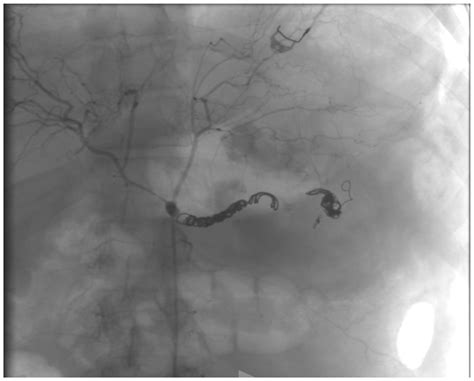

Angiography: Involves injecting a contrast dye into the blood vessels and taking X-ray images. It provides detailed images of the blood vessels and can help plan treatment.

Angiography is particularly useful for planning surgical or endovascular interventions.